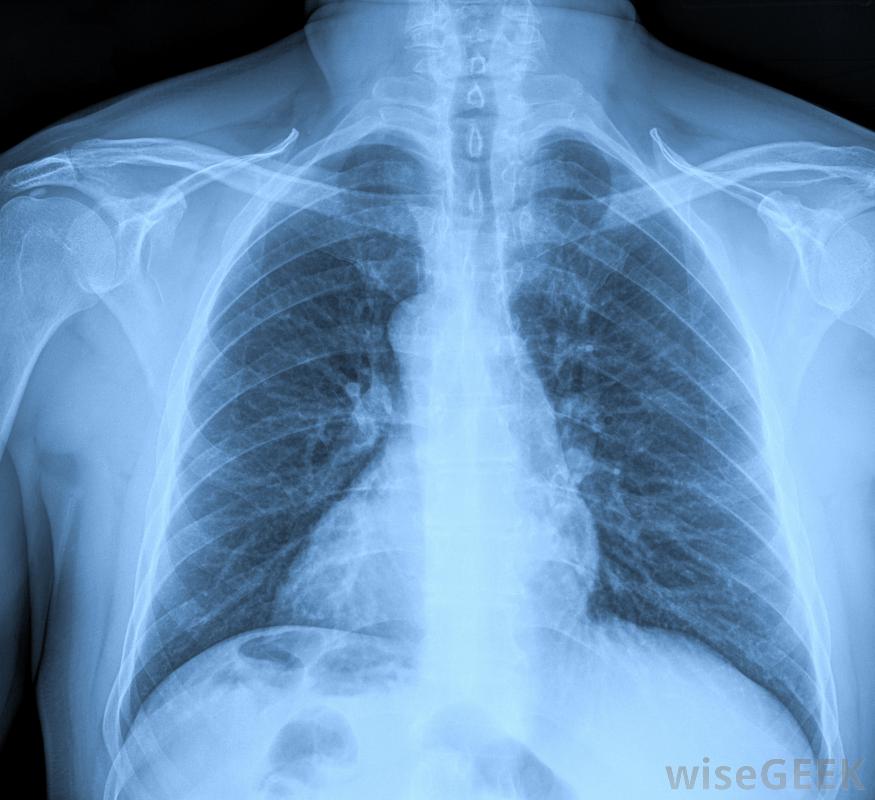

經口氣管插管時,醫生、護理人員或高級心臟生命支持(ACLS)提供者站在病人的頭上,倒立在病人的解剖結構上,用喉鏡的刀片將舌頭和會厭抬開。會厭保護氣管頂部或氣道,防止意外進入食物或液體。當被提起并讓開時,可以通過照亮的喉鏡刀片和插入氣管的呼吸管來識別氣管頂部的聲帶。因為食道-胃部的導管-與氣管相鄰,嘗試性的經口氣管插管可以很容易地將呼吸管引入食道而不是氣管。有幾種類型的評估用于確認呼吸管的正確放置,包括在適當的位置傾聽呼吸聲和胸部x光片(如有)。

呼吸管被固定住將靠近氣管末端的一個小燈泡充氣,使其處于適當的位置。將導管從患者口中伸出的地方用膠帶固定,并進行額外的捆扎以進一步固定氣管插管。如上所述,氣管插管的正確放置總是通過盡快的胸部x光片來確認。

胸部x光片用于確認呼吸管的正確放置。